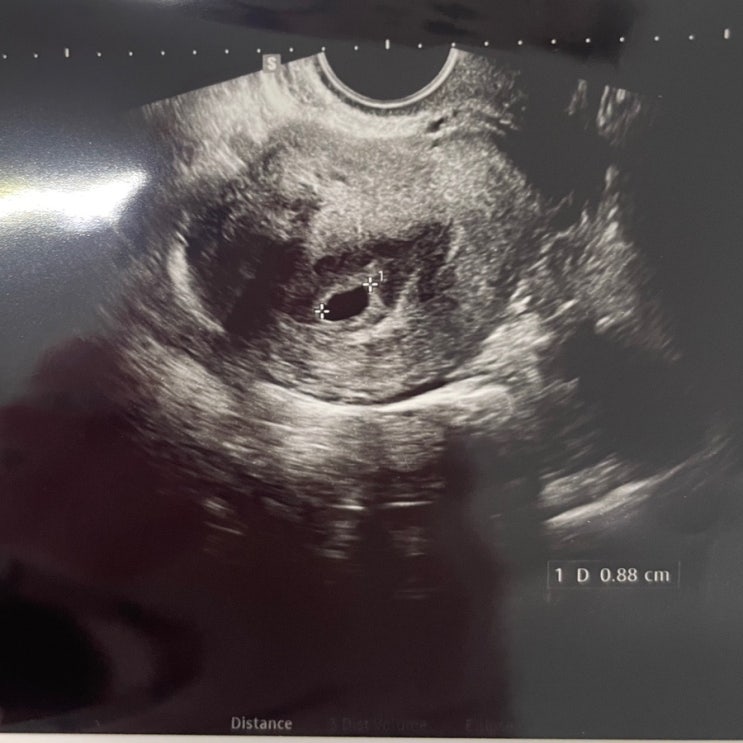

[시험관임신] 임신 피검 수치별 임테기 진하기 비교

언젠가 블로그 밀린 일기를 쓰게 되겠지만 나는 시험관 동결3차까지 진행하였고 두번의 유산 끝에 지금은 ...